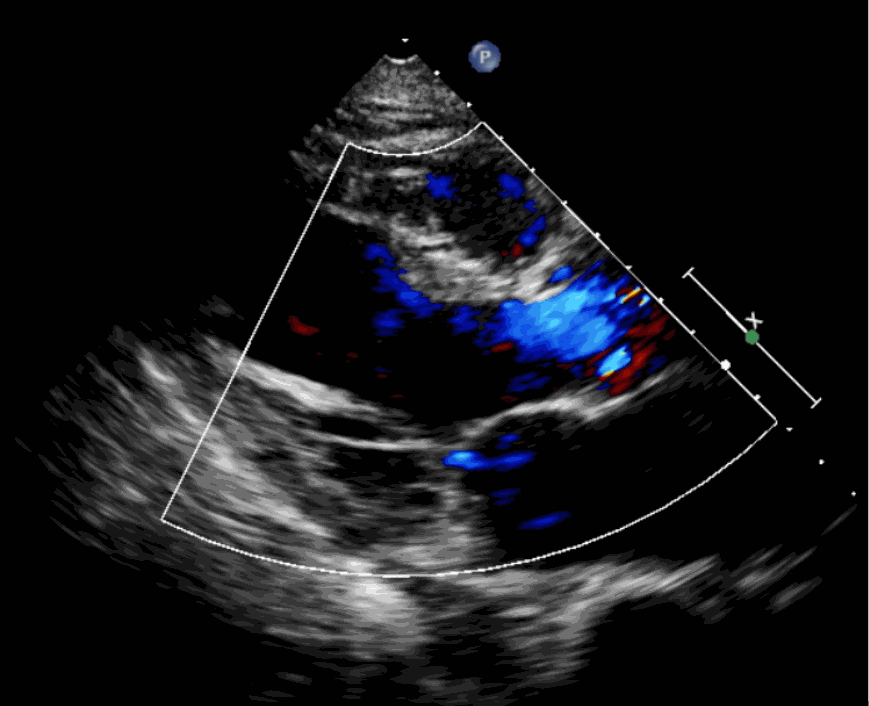

術(shù)前超聲影像圖

該例患者為62歲,女性,因“間歇性心悸、胸悶、氣短、胸痛1年,加重1周”之主訴入院。入院診斷:主動(dòng)脈瓣重度關(guān)閉不全,二尖瓣、三尖瓣輕度關(guān)閉不全,心功能III級(jí);冠狀動(dòng)脈粥樣硬化性心臟病。行心臟超聲心動(dòng)圖提示“主動(dòng)脈瓣重度關(guān)閉不全;瓣口水平以下左室下壁、后下壁搏幅減低;EF值 0.30,左房、左室大、右房大小正常高限;二尖瓣、三尖瓣關(guān)閉不全;輕度肺動(dòng)脈高壓(收縮壓42mmHg);主動(dòng)脈硬化;左室收縮功能重度減低。經(jīng)心血管外科劉洋、楊劍教授、麻醉科陳敏教授及超聲科孟欣教授等專家團(tuán)隊(duì)綜合評(píng)估,判定患者為外科手術(shù)高危患者。